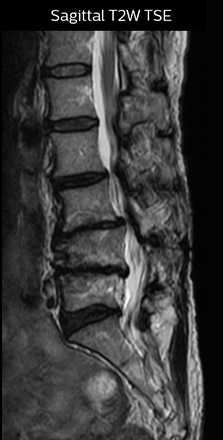

“For example, in sagittal images, when the presence of fat is observed in the intervertebral foramen, it suggests that there is a margin around the nerve. Similarly, the absence of fat indicates that the nerve is being compressed. So, we used to deduce nerve compression indirectly. With NerveVIEW, however, we can observe the condition of the nerves directly, regardless of the presence or absence of fat. We always prefer such direct observation of anatomy over having to make an inference about it.”

The key concept in MR neurography, Dr. Yabuki stresses, is the ability to directly visualize spinal nerves, versus inferring the presence of pathology indirectly. “Before NerveVIEW, we estimated compression of the nerve by looking for the presence or absence of fat signal on other MR images,” he says.

“Before NerveVIEW, diagnosis by MRI alone was sometimes difficult, unless there was a strong suspicion based on clinical symptoms,” says Shoji Yabuki, MD, DMSc, Orthopedic surgeon at Fukushima Medical University School of Medicine. “This is why we routinely perform selective lumbosacral radiculography (nerve root block) and x-ray in such cases. However, radiculography can only depict nerves as far as the contrast agent reaches. When a nerve is distorted by compression, the contrast agent will not pass through this compressed area, preventing us from evaluating the full nerve compression.”